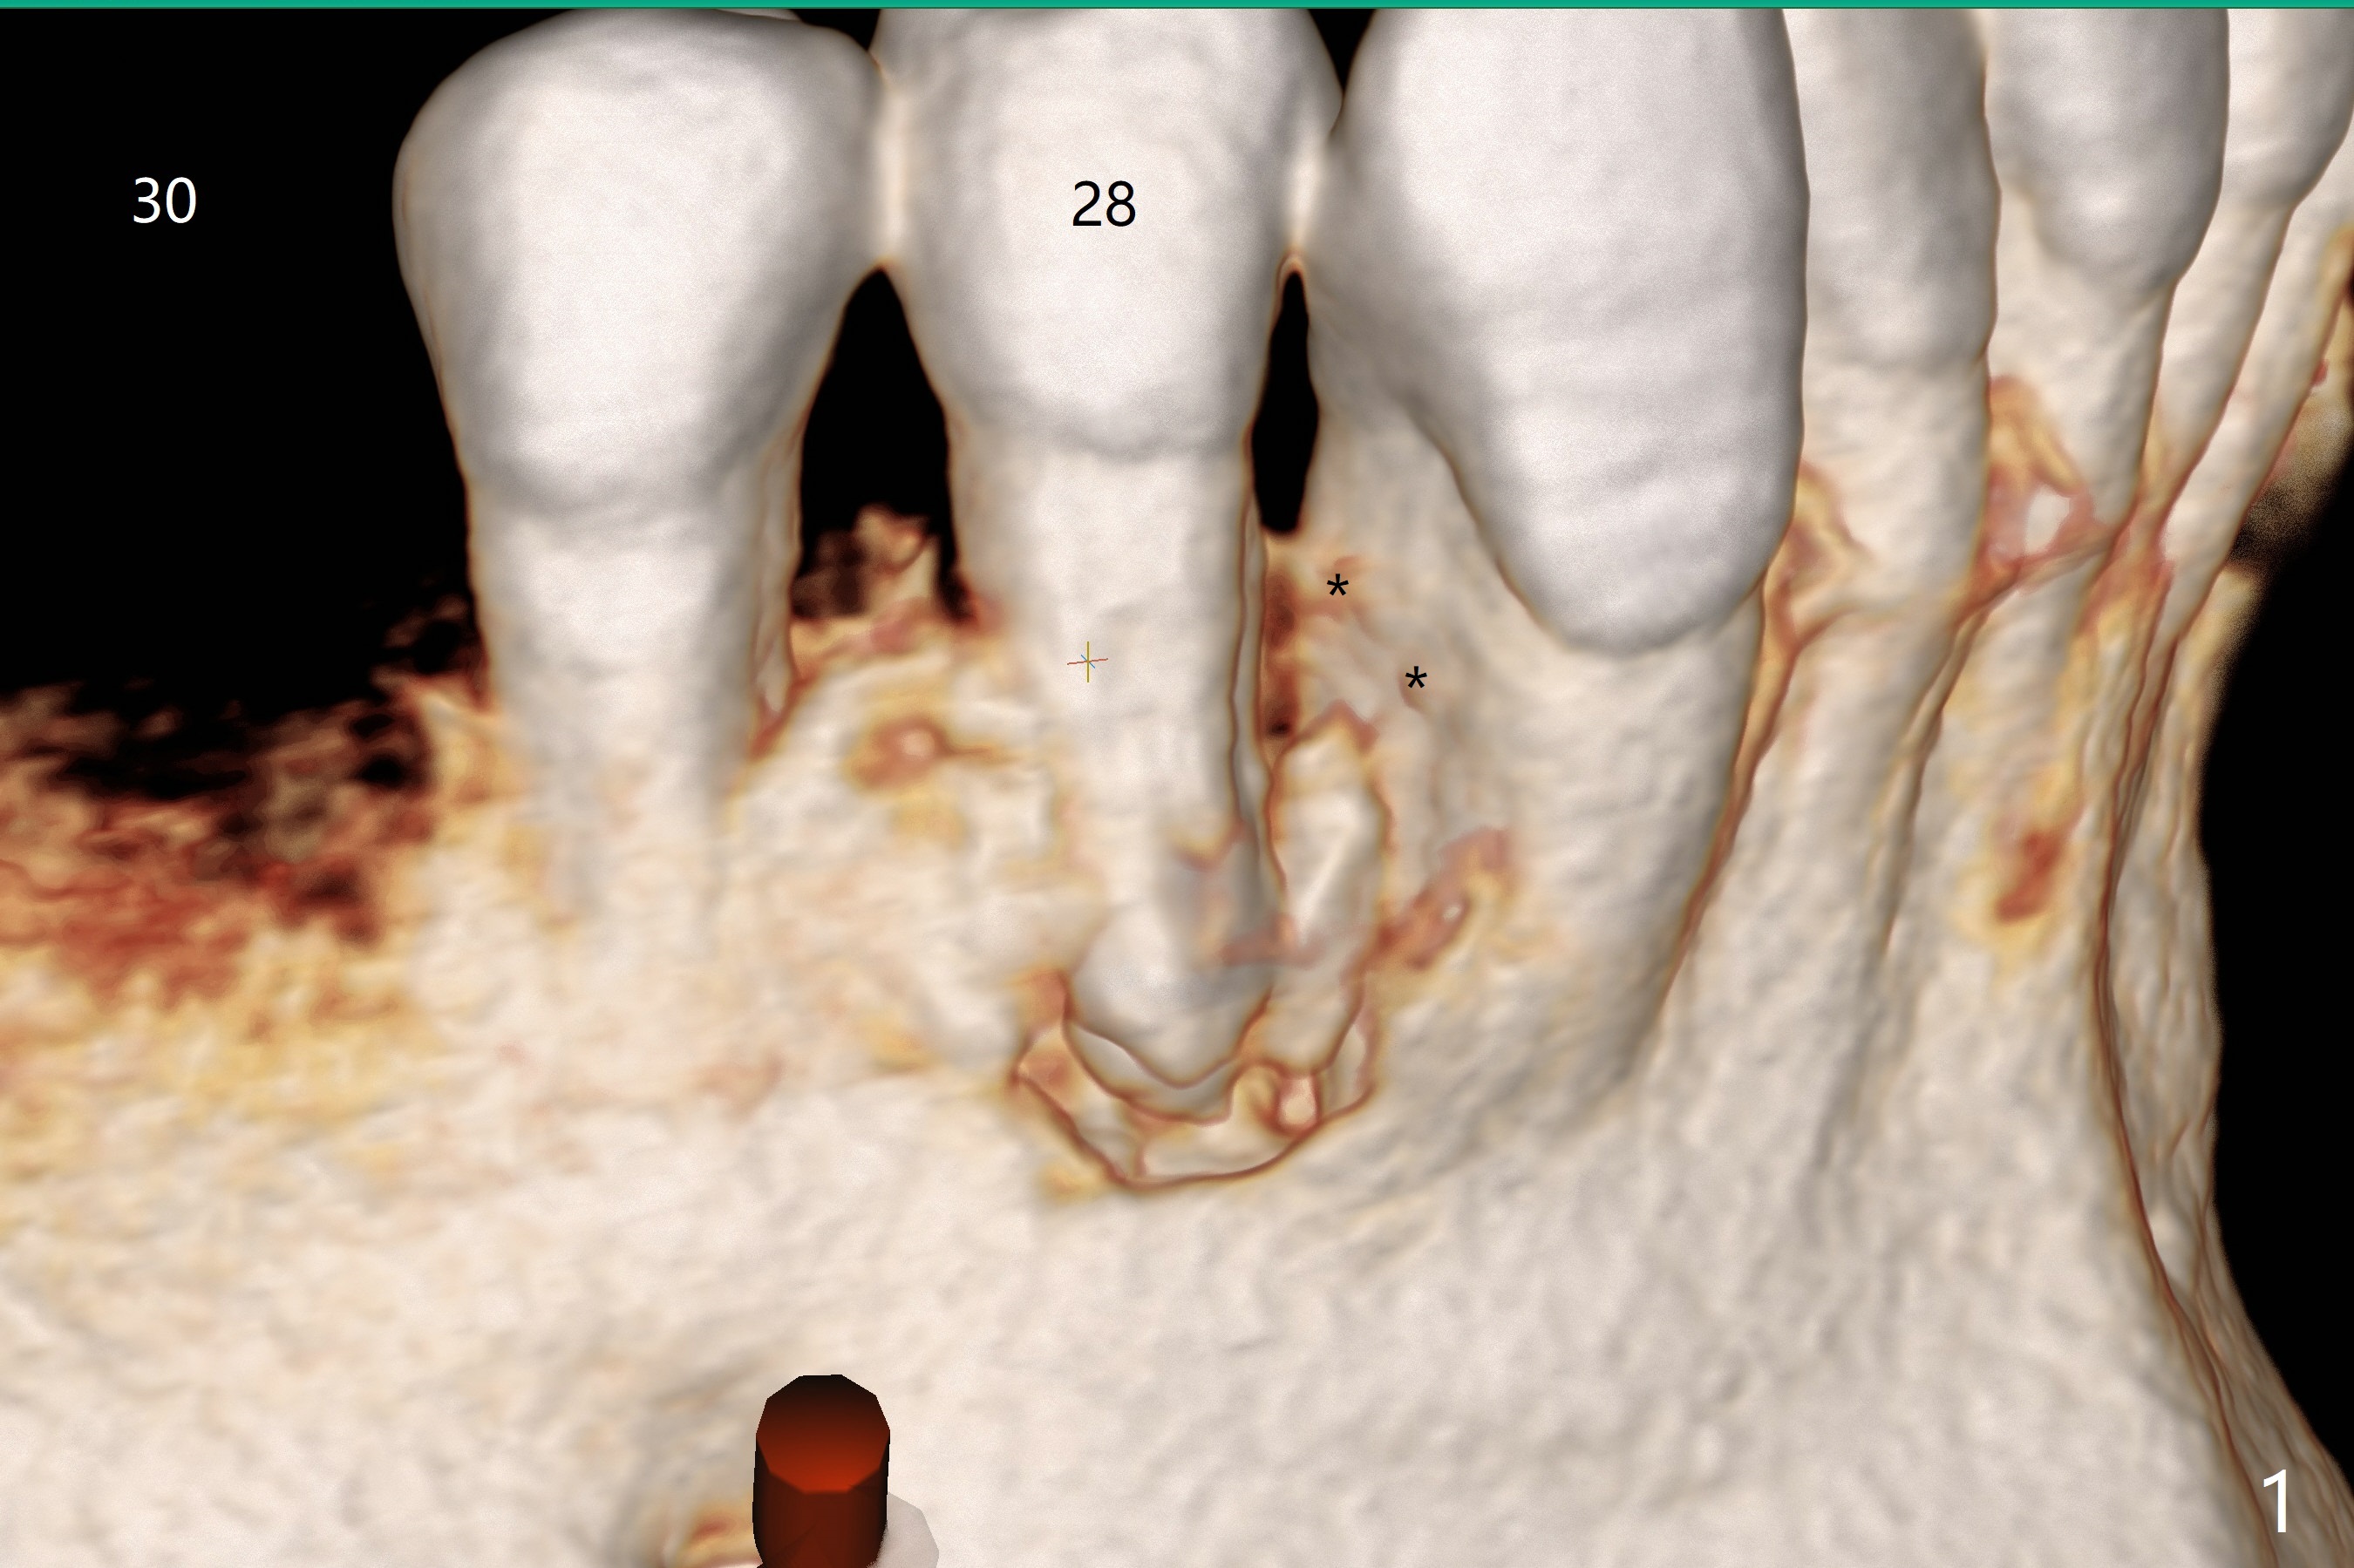

A -year-old man seeks treatment for the tooth #28 with severe bone loss (Fig.1 islands of bone remaining in the mesial surface of the tooth #27, reossification center for grafted bone). The tooth #28 has oblique root fracture (Fig.2 lingual view). One of treatment options is to place an immediate implant (green) at #28 as lingual as possible (Fig.3,4 (coronal section, after extraction (black area))). Sticky bone is placed buccal (Fig.5 red); some of bone graft will be pressed into the space between implant threads (arrowheads, bone and implant contact area expectedly to be higher than delayed placement due to less pressure to the native bone). In spite of severe bone loss between #27 and 28 (Fig.6 (sagittal section) after extraction), the crestal bone appears to exist in the mesial surface of #27 (*). With placement of an abutment (Fig.7 pink) and an immediate provisional (white), bone graft is packed as high as supracrestal (red). Restoration of the crest is expected to be better than socket preservation.